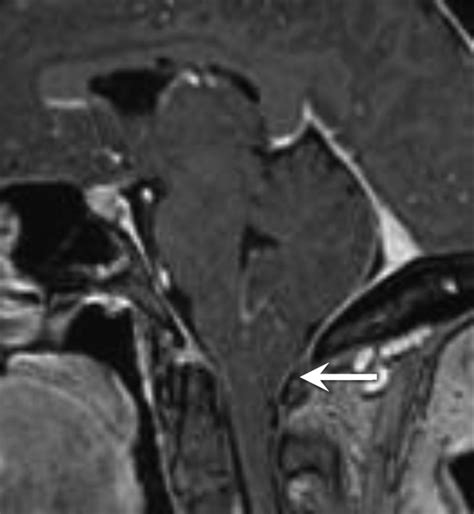

At its core, Cerebellar Tonsillar Ectopia describes the displacement of the cerebellar tonsils into the upper spinal canal. While often used interchangeably with Chiari malformation, it is important to note that the term "ectopia" typically refers to the physical descent of these structures. In many cases, this descent is identified incidentally during imaging studies like an MRI, performed for unrelated reasons such as persistent headaches or neck pain.

The primary concern with this condition is the crowding of the space at the base of the skull. Because the foramen magnum is a rigid, bony ring, any structure occupying space that should be reserved for fluid flow can lead to increased intracranial pressure. The degree of displacement is usually measured in millimeters, and while not every patient with this condition experiences debilitating symptoms, those who do often report complex neurological challenges.

The flow of cerebrospinal fluid is the "pulse" of the central nervous system. It acts as a shock absorber and clears waste products from the brain. In patients with Cerebellar Tonsillar Ectopia, the displaced tonsils may partially obstruct the narrow space where the CSF exits the skull. This blockage can create a bottleneck effect, leading to pressure buildup. When the fluid cannot circulate freely, it may lead to the formation of a syrinx—a fluid-filled cyst within the spinal cord—which can cause further neurological damage if left unaddressed.